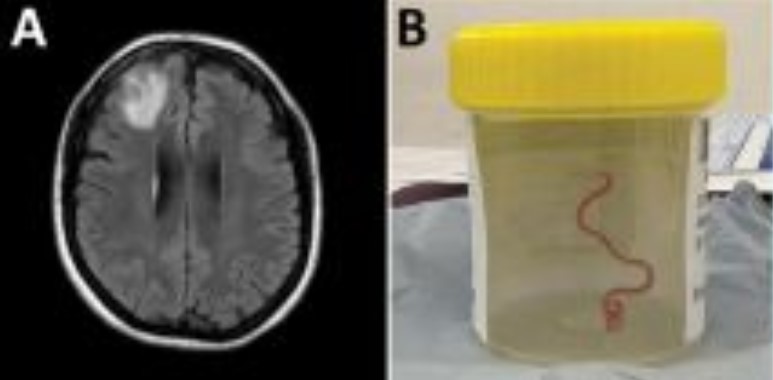

Raziskovalci Avstralske nacionalne univerze (ANU) in bolnišnice v Canberri so iz možganov 64-letne pacientke potegnili 8-centimetrskega parazita, ki je bil živ in se je premikal, poročajo tuji mediji.

Neimenovana pacientka iz jugovzhodnega Novega Južnega Walesa v Avstraliji je bila prvič v bolnišnico sprejeta konec januarja 2021, potem ko je že tri tedne trpela zaradi bolečin v trebuhu in driske, ki so jim sledili stalni suh kašelj, vročina in nočno potenje. Čez eno leto je znova obiskala zdravnika in poročala o pozabljivosti in depresiji, zaradi česar jo je zdravnik poslal na slikanje možganov. Slika je pokazala nepravilnosti v desnem čelnem režnju, zato so se zdravniki odločili za operacijo.

"Vsi v operacijski dvorani so doživeli šok. Kirurg je vzel klešče, da bi odstranil nepravilnosti, izkazalo pa se je, da je ta nepravilnost živ 8- centimetrski svetlordeč zajedalec," je za BBC povedal Sanjaya Senanayake, infektolog iz bolnišnice v Canberri.

Parazit z znanstvenim imenom Ophidascaris robertsi pogosto napada avstralske pitone (angl. Carpet python), ki živijo v večjem delu Avstralije. "Kolikor vemo, je to tudi prvi primer, ki vključuje možgane katerekoli vrste sesalcev," je še povedal Senanayake. Parazit običajno živi v pitonovem požiralniku in želodcu, jajčeca pa leže v gostiteljevem blatu. Zato raziskovalci domnevajo, da je ženska jajčeca parazita vnesla v telo z uživanjem rastline, imenovane novozelandska špinača (lat. Tetragonia tetragonioides), ki jo je nabirala ob jezeru blizu mesta, kjer je živela, in na katero je piton izločil zajedalčeva jajčeca.